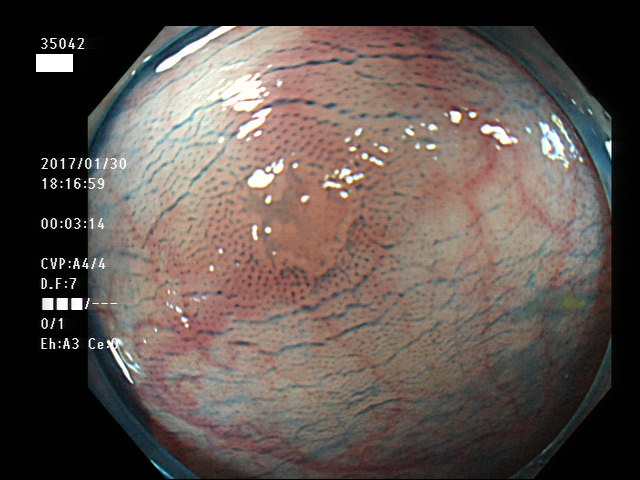

上記100名より抽出した平坦・陥凹型腺腫・SSAP(=癌化の危険が高いが見落としやすい病変)の内視鏡写真

35022 35023 35025 35027 35028 35029 35030 35033 35035 35036 35038 35042